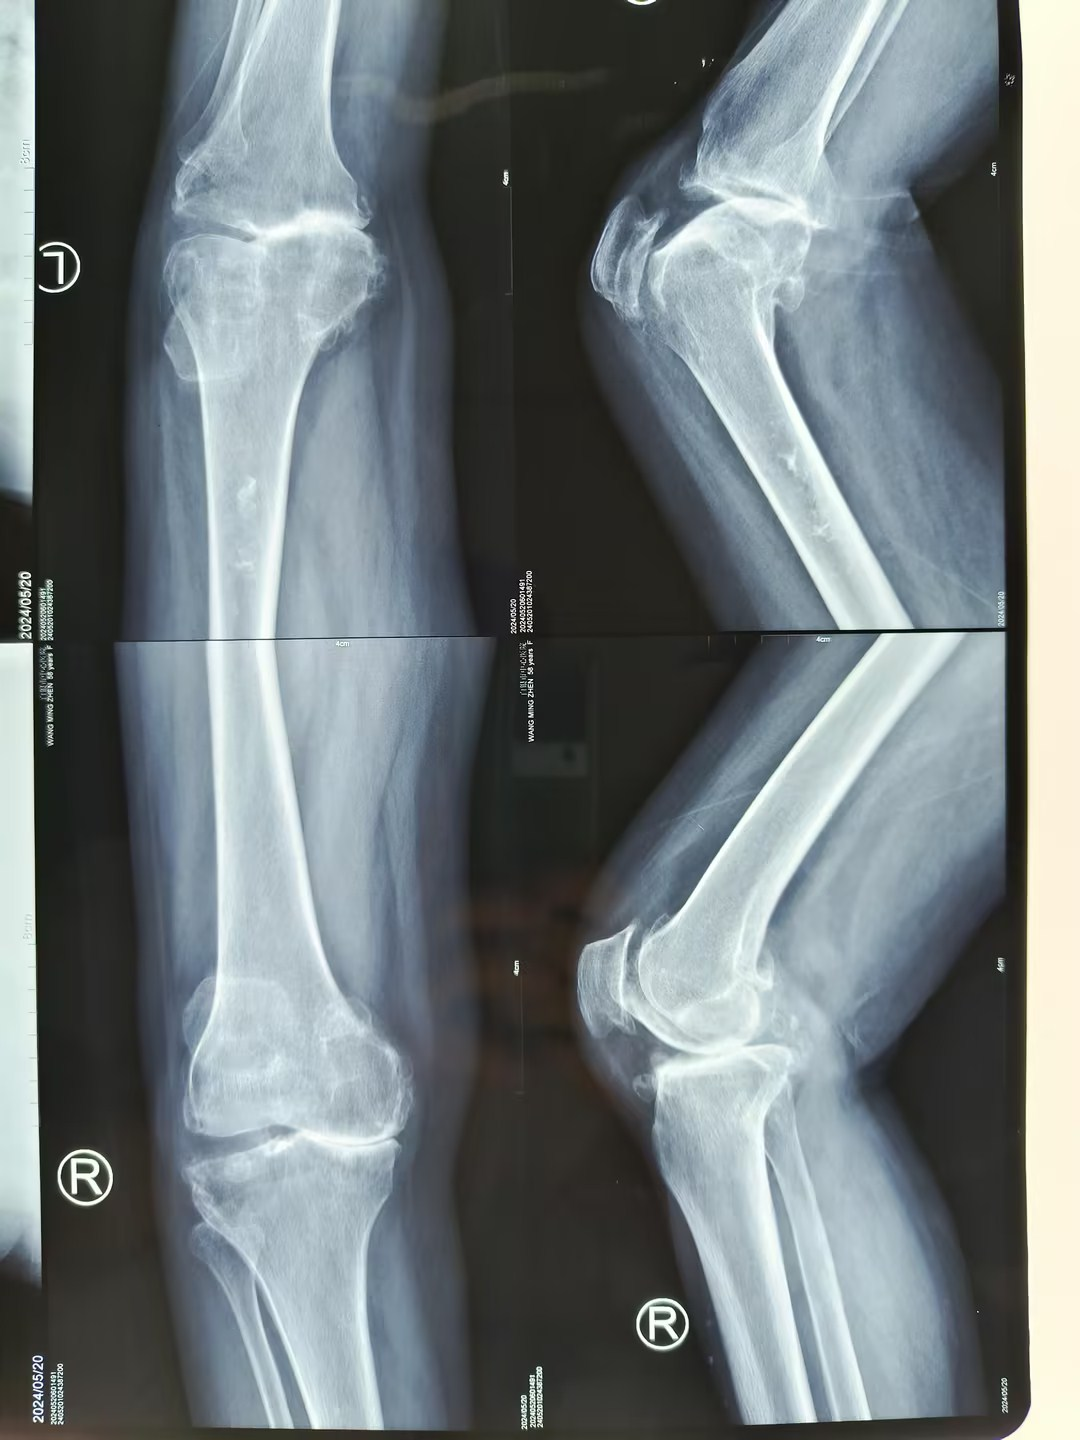

在创伤骨科住院后,经安勇主任医师团队诊断,王先生为双侧膝关节骨性关节炎,双侧膝关节内翻畸形。结合病史及影像学检查,考虑行双侧膝关节置换手术,因王先生左膝疼痛较右膝疼痛明显,所以先行左膝关节置换手术,术后10天,患者左膝疼痛减轻后,再行右膝膝关节置换手术。手术取得圆满成功,解除了王先生十余年的病痛。